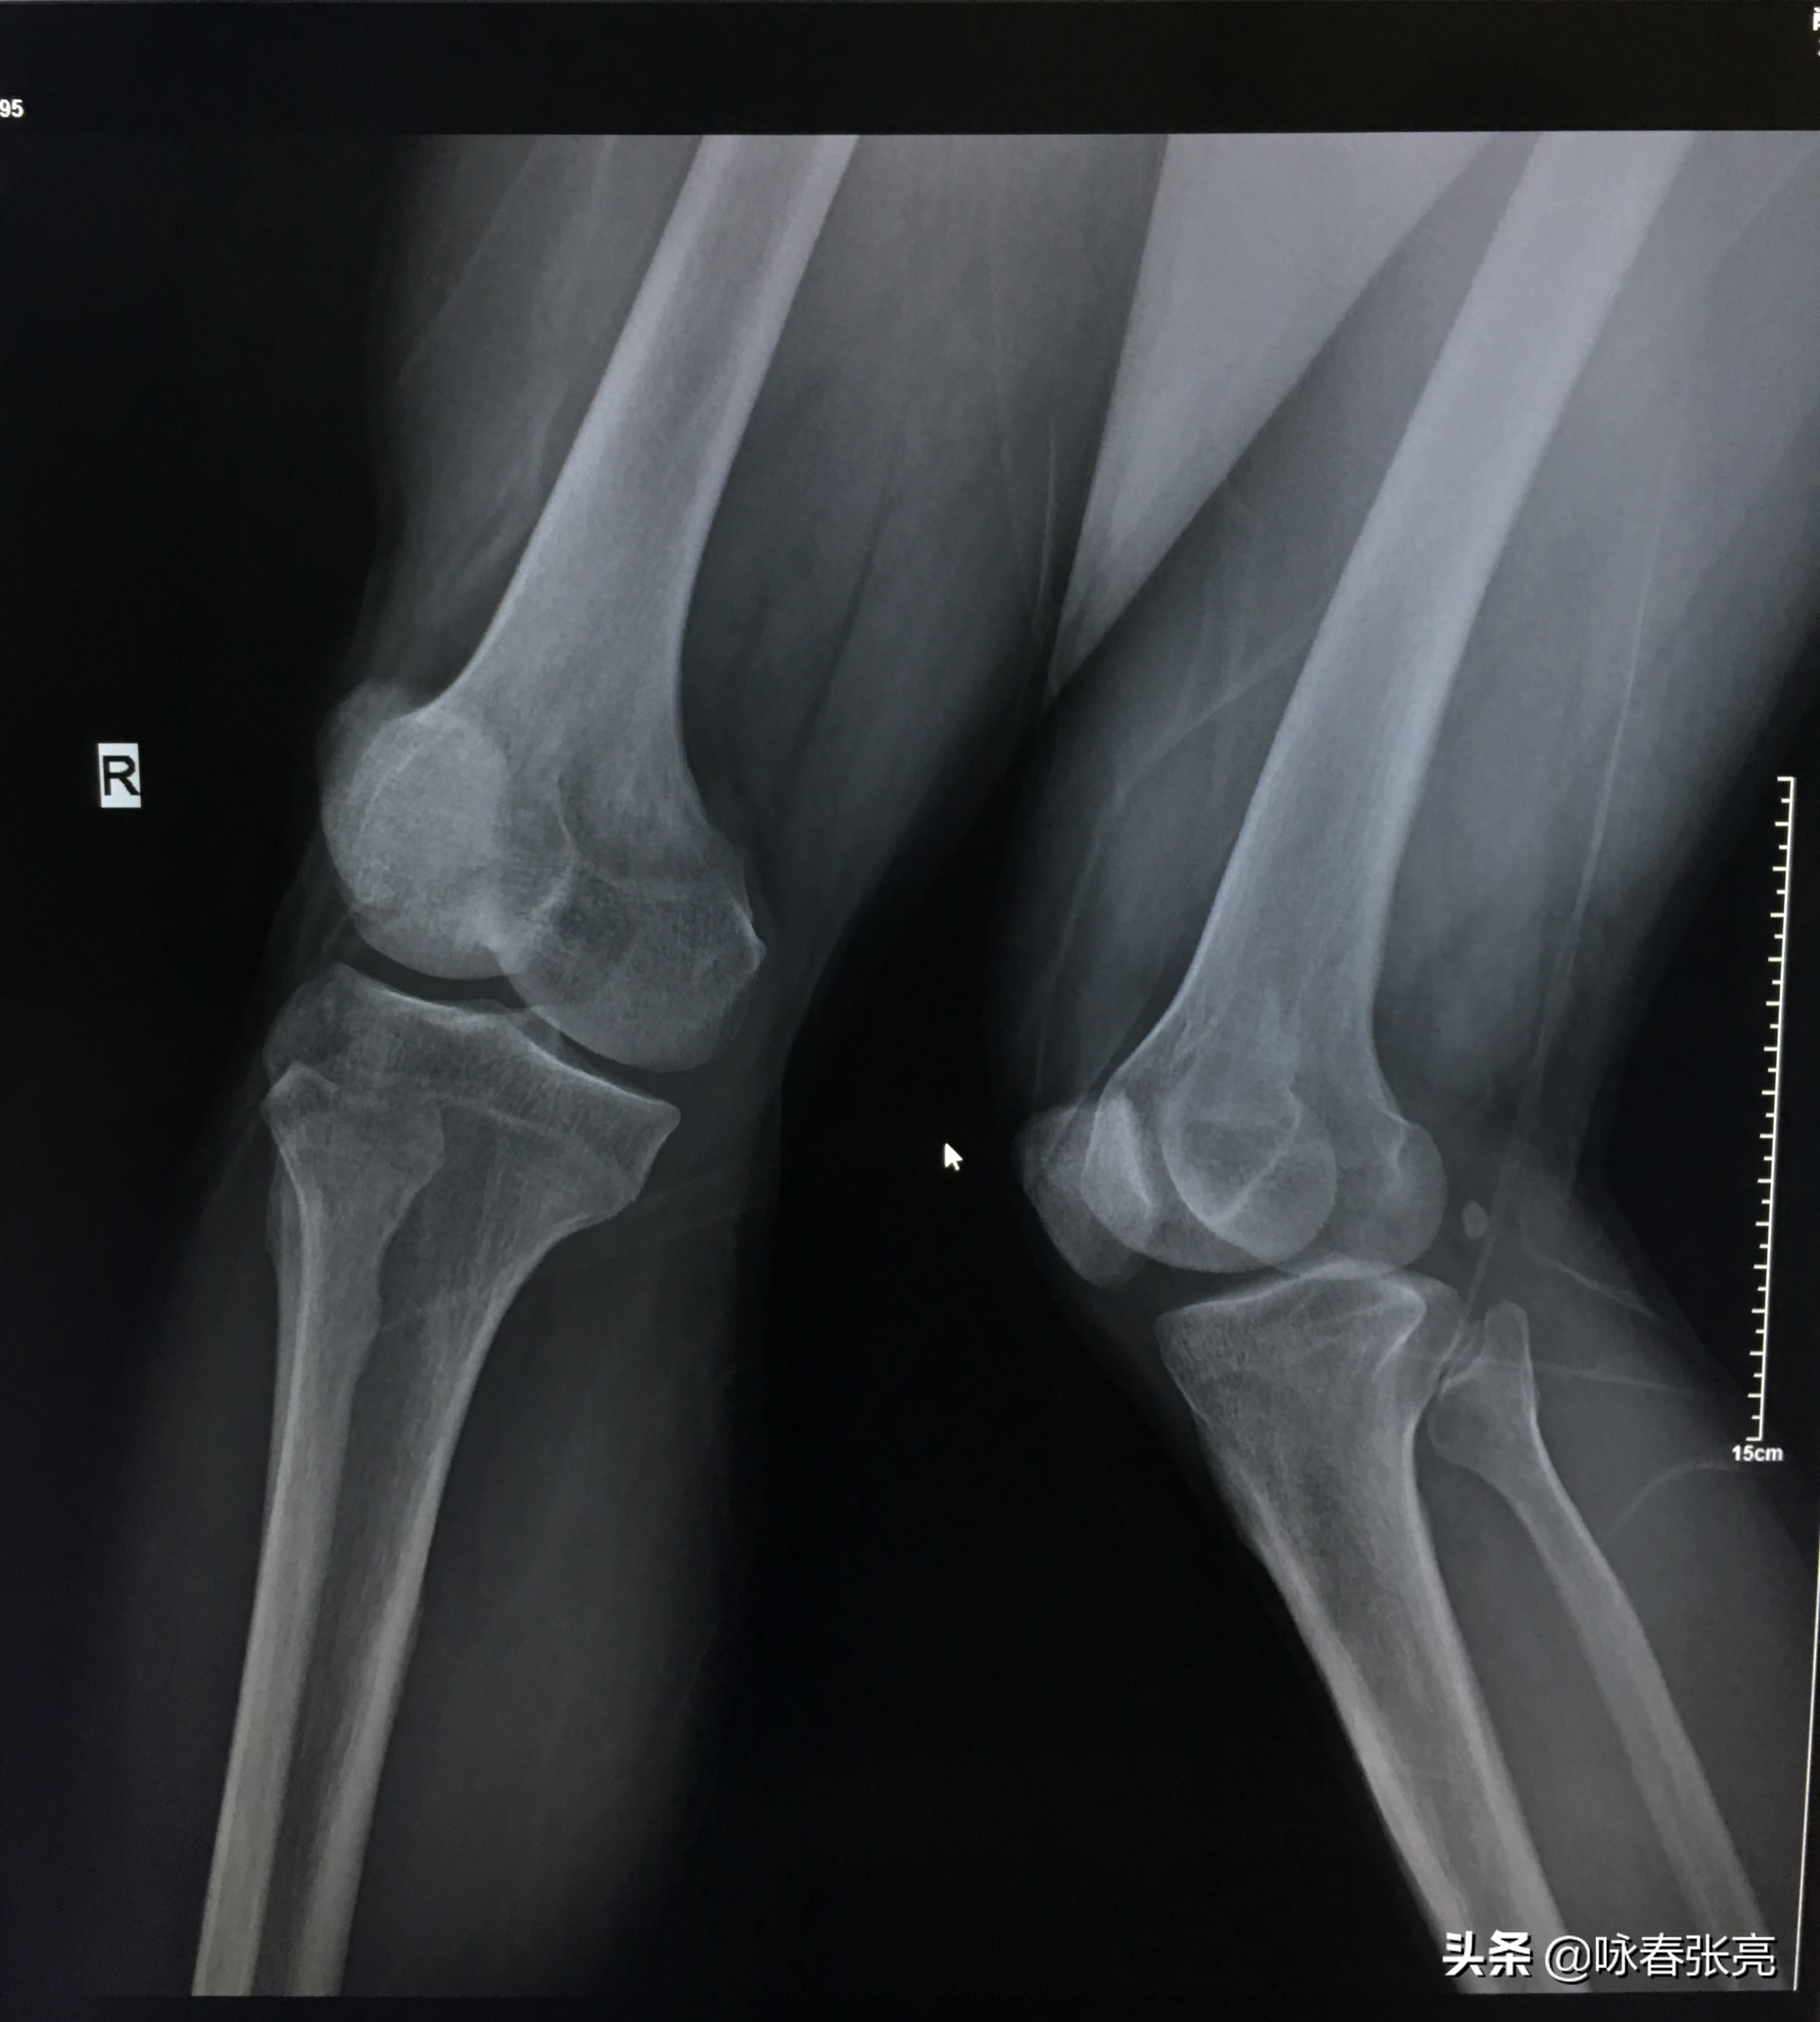

咏春拳二字钳羊马 DR